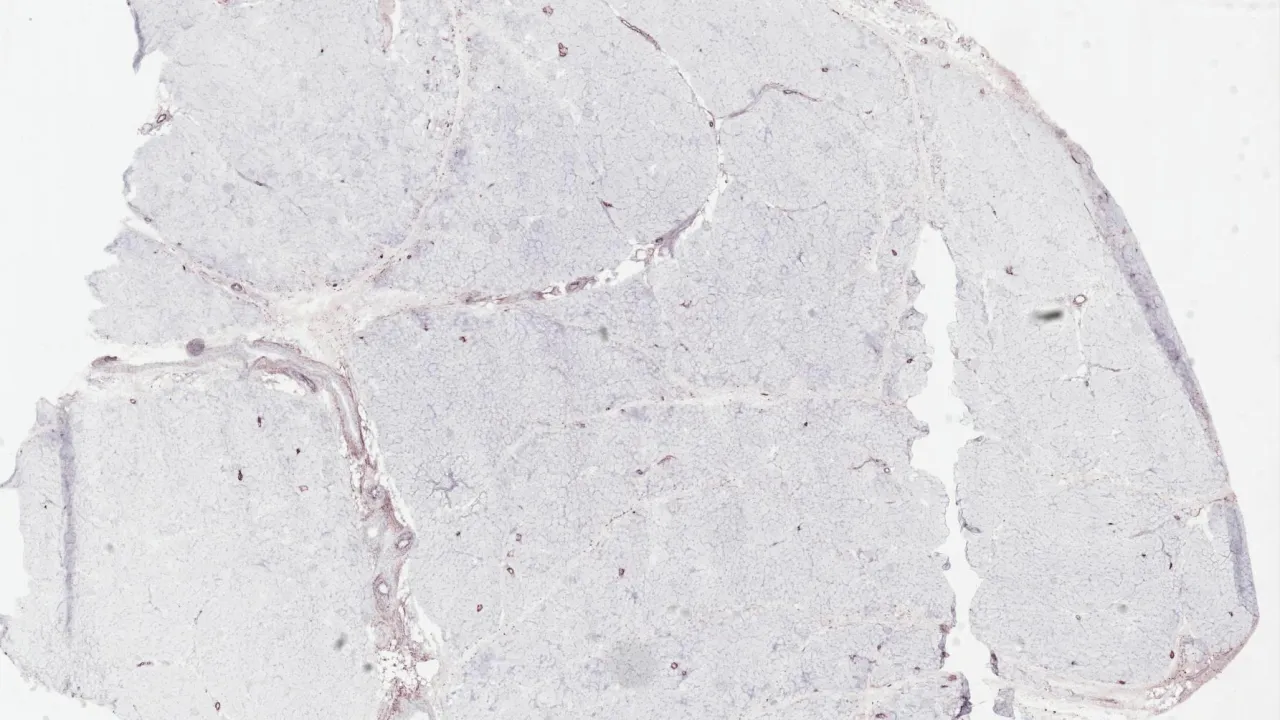

Testis, Mixed germ cell tumour, B-HCG stain

Testis, Mixed germ cell tumour, CD30 stain

Testis, Mixed germ cell tumour, Glypican stain

Testis, Mixed germ cell tumour, H&E stain